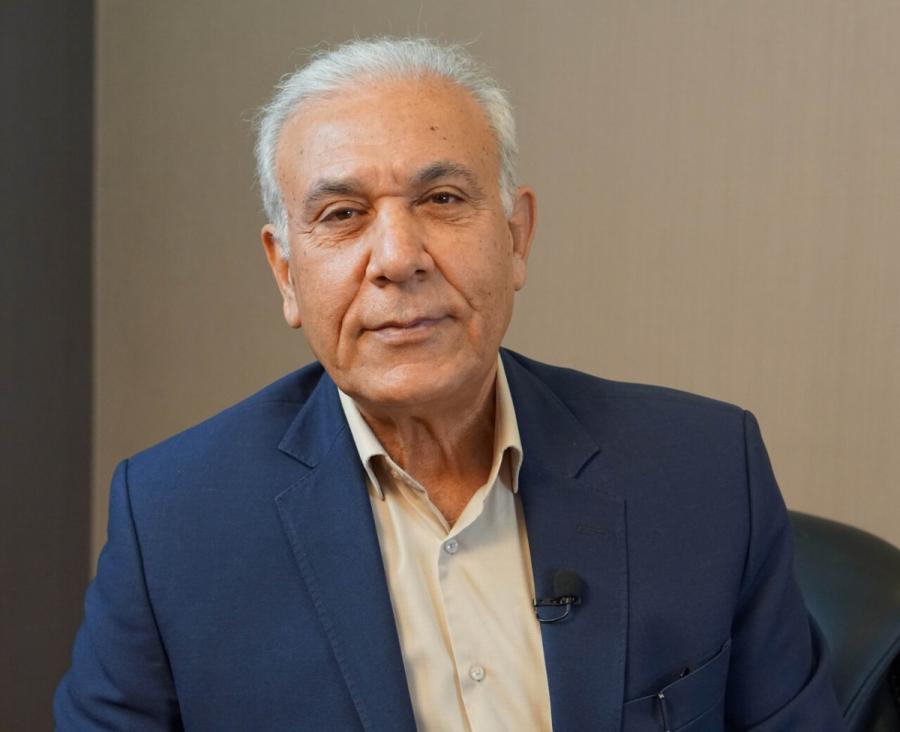

رئیس هیات مدیره انجمن علمی تخصصی باروری و ناباروری ایران و فلوشیپ نازایی در پاسخ به این که آیا تعیین جنسیت ۱۰۰ درصد جواب میدهد، میگوید: اگر علمی برخورد کنیم، تعیین جنسیت ۱۰۰ درصد جواب میدهد. چون ما از ابتدا جنسیتِ مثلا پسر را در رحم زن میگذاریم. فقط بستگی دارد که زن با روش IVF بارور شود که همان طور که گفتم، احتمال باروری با این تکنیک فقط ۳۷ درصد است.

بسیاری از مردم تصور میکنند که روش کمک باروریِ IVF تنها برای زنان بالای ۴۰ سال است که سن طلایی بارداری را پشت سر گذاشتهاند و احتمال باروری آنها به شدت پایین آمده است. اما دکتر محمدابراهیم پارسانژاد، فلوشیپ نازایی (IVF) و رئیس هیات مدیره انجمن علمی تخصصی باروری و ناباروری ایران به همشهری میگوید: اتفاقا برای انجام IVF، سن به هیچ وجه فاکتور مهمی نیست. اصلا IVF برای اولین بار که در دنیا ابداع شد، برای کسانی بود که لوله رحم خود را از دست داده بودند.

دکتر پارسانژاد میگوید: البته این یک واقعیت است که سن باروری در زنان فاکتوری بسیار مهم است. مردها کمتر از خانمها از فاکتور سن آسیب میبینند. بهترین سن باروری زنان بین ۲۳ تا ۲۸ سالگی است. این چیزی است که WHO (سازمان جهانی بهداشت) میگوید. به طوری که احتمال حاملگی در بالای ۳۵ سالگی در زنان پایین میآید. چه به طور طبیعی و چه با درمانهای کمکباروری. البته در سن بالای ۴۰، باروری زن غیرممکن نیست ولی اگر اتفاق افتاد، باید خیلی مراقب او باشیم.

دکتر پارسانژاد تاکید میکند: اصلا دقیق نمیشود گفت مشکل ناباروری دقیقا از زن است یا مرد اما طبق مطالعات قبلی، ۳۵ تا ۴۰ درصد علت نابارویها به آقایان و ۵۵ تا ۶۰ درصد علت ناباروریها به زنان مربوط است. در ۱۰ درصد موارد نیز هم مرد مشکل دارد و هم زن. علت ۱۰ تا ۱۵ درصد از مشکلات هم در هیچ یک از زوجین پیدا نمیشود که به آن میگویند «علت ناباروری با علت ناشناخته».

دکتر پارسانژاد میگوید: درمانهای همه اینها مشخص و موجود است اما با همه درمانها همچنان ۱۵ درصد از بیماران و حتی بیشتر بارور نمیشوند. اینها کسانی هستند که برای بارور شدن به روش IVF نیاز دارند.

به گفته این فلوشیپ نازایی، روش IVF در بهترین مراکز ناباروری دنیا هم تنها حدود ۳۰ تا ۳۷ درصد جواب میدهد؛ یعنی از حدود ۱۰۰ زوج که IVF انجام میدهند، فقط ۳۷ درصد (حدود یکسوم) بارور میشوند.

دکتر پارسانژاد روی این نکته تاکید میکند که همه زنان به IVF نیاز ندارند. کمتر از ۱۰ درصد یا حدود ۱۰۰ نفر از زنان نابارور برای باروری به IVF نیاز پیدا میکنند.

این فلوشیپ نازایی در پاسخ به این که آیا تعیین جنسیت ۱۰۰ درصد جواب میدهد، میگوید: اگر علمی برخورد کنیم، تعیین جنسیت ۱۰۰ درصد جواب میدهد. چون ما از ابتدا جنسیتِ مثلا پسر را در رحم زن میگذاریم. فقط بستگی دارد که زن با روش IVF بارور شود که همان طور که گفتم، احتمال باروری با این تکنیک فقط ۳۷ درصد است.

به گفته رئیس هیات مدیره انجمن علمی تخصصی باروری و ناباروری ایران، احتمال دوقلوزایی در روش IVF هفت تا هشت درصد و احتمال سهقلوزایی فقط دو درصد است. حالا نه این که هرکس سهقلو دارد، حتما IVF کرده است. من خودم سهقلو دارم و آن زمان هم IVF هنوز ابداع نشده نبود.

رئیس هیات مدیره انجمن علمی تخصصی باروری و ناباروری ایران درباره آمار تولد کودکان ایرانی به روش IVF توضیح میدهد: آمار دقیقی از این که چه تعداد کودک در ایران از طریق IVF به دنیا آمدهاند، نداریم.

رئیس هیات مدیره انجمن علمی تخصصی باروری و ناباروری ایران درباره تعداد دفعاتی که میتوان روش IVF را برای باروری انجام داد، میگوید: این تکنیک سقفی ندارد و بستگی به قرارداد و گایدلاین هر کشوری دارد. هنوز در هیچ جای دنیا قانونی نیامده که تعیین کند چند بار IVF کافی است. ممکن است تا ۹ بار هم IVF را برای بیمار تکرار کنیم و بار آخر باردار شود. بعضیها هم با IVF اول حامله میشوند. ولی همانطور که گفتم، سقف و محدودیتی ندارد.

رئیس هیات مدیره انجمن علمی تخصصی باروری و ناباروری ایران درباره هزینههای IVF میگوید: درباره هزینهاش چیزی نگویم بهتر است. مثلا در تهران برای یک IVF باید تمام زندگیات را بدهی ولی در شهرستانها هزینهاش کمتر از عمل آپاندیس درمیآید.